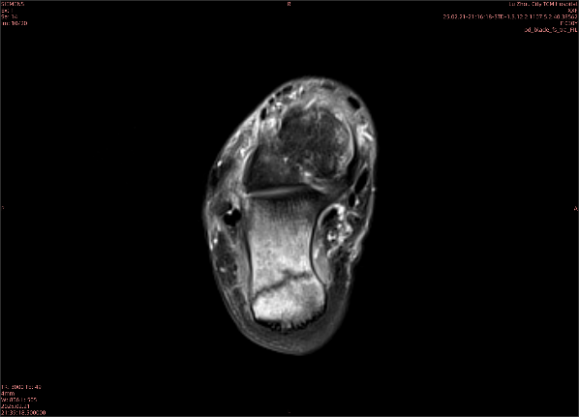

隱性骨折在MRI表現(xiàn)為T1WI序列上見由關(guān)節(jié)面向骨干走行的形態(tài)各異低信號區(qū),有線狀、條狀、紊亂低信號,信號強(qiáng)度不均勻。與T1WI低信號改變相對應(yīng)部位在T2WI上表現(xiàn)為相應(yīng)形狀的高、低混雜信號,且部分低信號周圍可見高信號水腫改變。STIR序列圖像上病灶呈顯著高信號,與信號被抑制的臨近正常骨髓形成鮮明對比,分界也較T2WI成像更為清楚。脂肪組織抑制技術(shù)是MRI的一個重要性能,脂肪抑制技術(shù)在MRI應(yīng)用中可以改善組織對比和增加病變顯示機(jī)會,這樣骨髓的脂肪抑制后就不會有任何信號,而隱性骨折線及骨髓水腫的異常高信號就會更加明顯的顯示出來。

舉例圖像

圖1

專業(yè)解釋看不懂沒關(guān)系,大家看圖1和圖2就可以了,這是同一個患者跟骨的磁共振和CT圖像,圖1的紅色箭頭指示的黑線就是磁共振圖像顯示的骨折線,一目了然。而對比圖2的CT圖像上并未顯示異常。